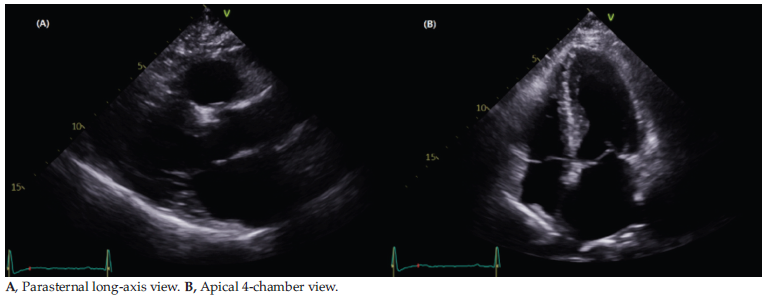

A 55-year-old female patient with alcoholic liver disease (Model of End-Stage Liver Disease sodium score 26, body weight 80.7 kg, height 158.6 cm) underwent a living donor LT, with her 34-year-old son serving as the donor. Her history included hepatorenal syndrome, refractory ascites (requiring percutaneous drainage), and left lower leg cellulitis. The patient underwent routine preoperative evaluation at our institution, including electrocardiogram, adenosine technetium Tc-99m single-photon emission computed tomography myocardial perfusion imaging, and transthoracic echocardiography. Preoperative elec-trocardiography showed normal sinus rhythm, and chest radiography demonstrated normal heart size with no remarkable findings. Cardiac evaluation, including single-photon emission computed tomog-raphy myocardial perfusion imaging and coronary computed tomography, revealed no abnormalities. Routine preoperative transthoracic echocardiography showed a hyperdynamic left ventricle with normal systolic function and ejection fraction of 72%. The mitral valve had unremarkable morphology with trivial regurgitation, and continuous-wave Doppler ultrasonography of the LVOT demonstrated peak systolic flow velocity of 1.65 m/s. The interven-tricular septum and left ventricular posterior wall thicknesses during diastole were 7.4 mm and 8.7 mm, respectively (Figure 1).

Figure 1. Preoperative Transthoracic Echocardiography